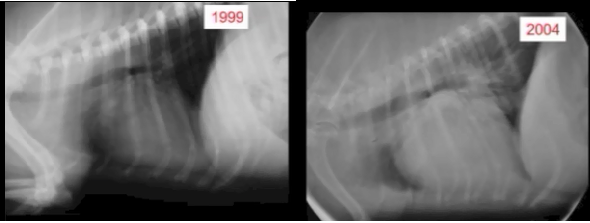

Radiography (x-ray) is used to determine if the heart is enlarged

(particularly the left atrium and left ventricle), if the veins from the

lungs to the heart are distended, or if fluid is beginning to develop in the

lungs.* X-rays also will show any enlargement of

the pulmonary vein, a classic symptom of congestive heart failure (CHF).

Once a mitral valve murmur is detected by auscultation, annual x-rays are very useful in charting the progression of the disease. The 2009 ACVIM "Consensus Statement" on degenerative MVD recommends baseline thoracic radiography for dogs with a new mitral valve murmur, then annually thereafter. However, if auscultation by stethoscope indicates that a murmur has remained mild -- Grade 1 or 2 -- and has not progressed in loudness since the murmur was first detected, a set of follow-up x-rays the next year usually is not necessary.

• Using radiography to diagnose heart enlargement

Mild to moderate heart enlargement indicates mild to moderate progression of mitral regurgitation (MR), with the heart compensating for the effects of mitral regurgitation by enlarging. Usually the dog displays no outward signs or symptoms of MVD when moderate to severe heart enlargement develops, until the dog reaches the stage of heart failure.

The VHS is not intended to diagnose CHF. It's purpose is to enable veterinarians to more accurately determine enlargement of the heart (called cardiomegaly or dilation) and the progression at which the enlargement is occurring, which usually is due to MVD. However, since MVD normally initially causes only the left atrium (LA) to enlarge, the VHS method is not precise enough to measure only the size of the LA. See for example, the x-ray at left, which shows that the VHS measurements entirely miss the bulbous enlarged LA in the upper right corner of the heart. (Image from Hezzell, 2018.)

The VHS method is most effective when it is used to compare two x-rays of the same dog's heart, taken over time, to see if the later x-ray's VHS value is higher than the earlier one, thus indicating that an enlargement of the heart has occurred. Therefore, once an MVD murmur is first detected, it is advisable to obtain an initial set of chest x-rays (called a "baseline" set) for comparison with subsequent x-rays once progression of the MVD is suspected.